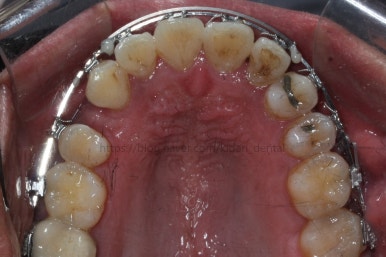

드디어 치료 종료시의 모습입니다. 2년 4개월 걸렸네요.

앞니 안쪽에는 유지철사를 붙여주었고요. 임플란트가 필요한 부위랑 맞닿은 부분은 치열이 움직이지 않도록 철사로 잡아주었어요.(오른쪽 어금니 부위)

삐뚤었던 치아들이 가지런해졌습니다.

왼쪽 송곳니를 발치했지만 별로 표시가 안나게 마무리를 했습니다.

많이 썩은 치아들은 다 뽑았고, 틈새도 다 다물어졌습니다.

원래 패여 있던 부위는 완벽하게 만들기는 힘들지만 앞으로 관리를 잘해주시면 이 모습 그대로 오래 사용하실 수 있으실거에요.